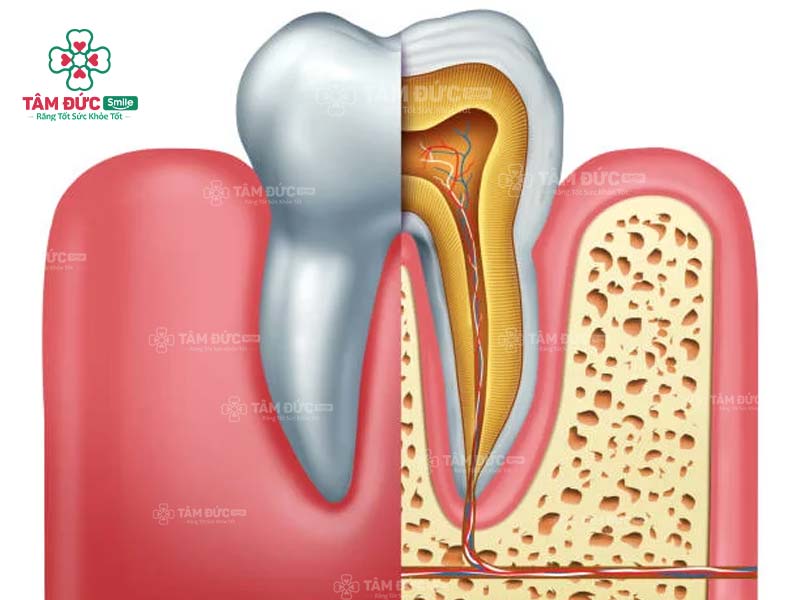

2.2. Tủy răng là nguồn nuôi dưỡng của răng

Tủy răng có chứa nhiều mạch máu, có chức năng lưu chuyển dưỡng chất để nuôi sống răng, cải thiện các tổn thương (nếu có) để giữ răng khỏe mạnh. Đây cũng là thành phần giúp răng chống lại các tác nhân gây hại.

Tuỷ răng đảm nhận vai trò nuôi dưỡng răng